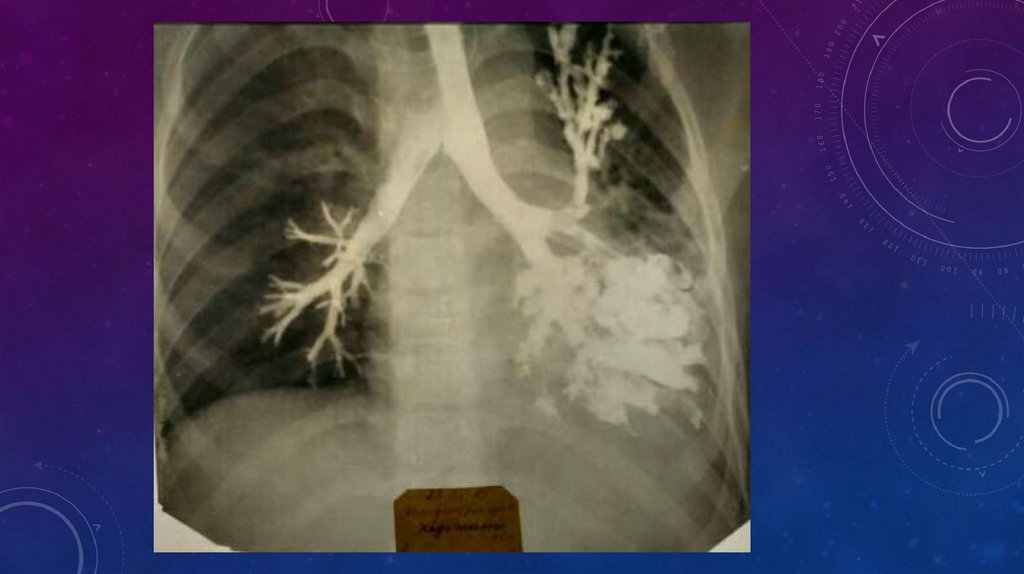

• В первую очередь проводят обзорную рентгеноскопию органов грудной клетки и

рентгенографию. Изменения, обнаруживаемые при этих исследованиях, зависят от

распространенности и тяжести поражения.

• Прямыми и достоверными рентгенологическими признаками бронхоэктазии служат ателектазы

или ячеистые просветления и кольцевидные («сотовидные») тени, соответствующие расширенным

бронхам. Подобные изменения при бронхоэктазии рентгенологически выявляются почти у 1/3

больных. Преимущественно отмечается поражение нижних долей, реже — средней доли и

язычковых сегментов. Соответственно и ателектазы наиболее часто отмечаются в области этих зон

легкого. Обычно ателектазы имеют вид треугольных теней, примыкающих одной стороной к

средостению. Особенно затруднительно выявление ателектаза нижней доли слева. Нужно учесть,

что тень ателектаза в этих случаях накладывается на тень сердца и наружная граница

ателектазированной доли контурируется в виде четкой полосы. При подозрении на ателектаз

средней доли показаны рентгеноскопия и рентгенография в положении гиперлордоза. При

тотальном поражении легкого отмечается некоторое уменьшение соответствующей половины

грудной клетки, сужение межреберных промежутков, затемнение соответствующего легочного

поля, особенно в нижних отделах, смещение средостения в сторону поражения.